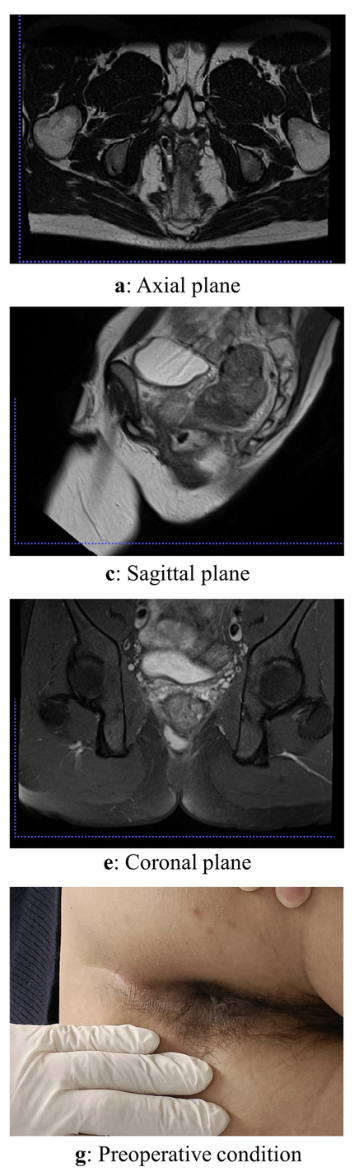

Ischiorectal abscess

- tend to be larger, indurated, and well-circumscribed

- located more laterally on the medial aspect of the buttocks

Remarks on ischiorectal abscesses

A

“Horseshoe abscess”

Can be problematic and complicated as the ischiorectal fossa forms a large potential space on either side of the rectum, communicating behind it through the deep postanal space